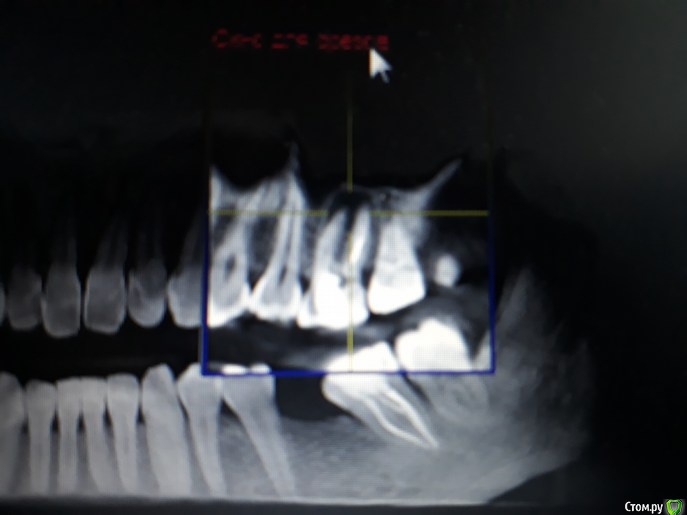

Викторри Опубликовано 18 февраля, 2018 Автор Поделиться Опубликовано 18 февраля, 2018 Беспокоит чувствительность только на тепло?8 недель уже каласепт? Ничего не меняется?Спасибо за ответ.На горячее-теплое, у меня впечатление,что не меняется. Каласепт уже 8 нед. Причем боль возникает не сразу при приеме горячего, а запоздало, постепенно расходится, как будто из эпицентра .Отчетливее всего она в 27 зубе,потом проходит. Мой лечащий врач утверждает,что реагирует выдвинувшийся 26 зуб именно у десны, моя постоянная врач говорит,что это 26 ,кто-то -за 28. Извините, что много ?. Насколько я поняла,при раскрытии кисты боль должна была пройти, но не прошла. Может ли быть причиной 28 зуб (там неск-ко врачей видели полость по рг) или все-таки проблема 26? На завтра мне назначена пломбировка 26 зуба. Насколько я поняла для пломбировки канал должен быть сухой ,соответственно если он не сухой, там есть проблем? м.б.,что каласепт не помог в течение такого времени или кисты могут долго болеть? Прикрепляю кт от 08.11.2107.Помогите разобраться: пломбироваться и ждать исчезновения болей или сейчас искать другой источник проблемы и после пломбир? Ответственность в принятии решения на мне, важно услышать ваше мнение. Спасибо. Ссылка на комментарий

DmitrySH Опубликовано 1 марта, 2018 Поделиться Опубликовано 1 марта, 2018 Не часто сюда захожу, соответственно и не отвечал. На след неделе иду в др.клинику.Если выяснится,что есть перфо,что делать? На представленых снимках перфо не видно. Пусть очно посмотрят, там и будет понятно. если во время лечения я почувствовала сильную боль, могла ли это быть перфорация,о ко-ой умолчали? по словам дока,это она дошла до верхушки. Я поверила. болезненные ощущения могли быть и при обработке верхушки. Ссылка на комментарий